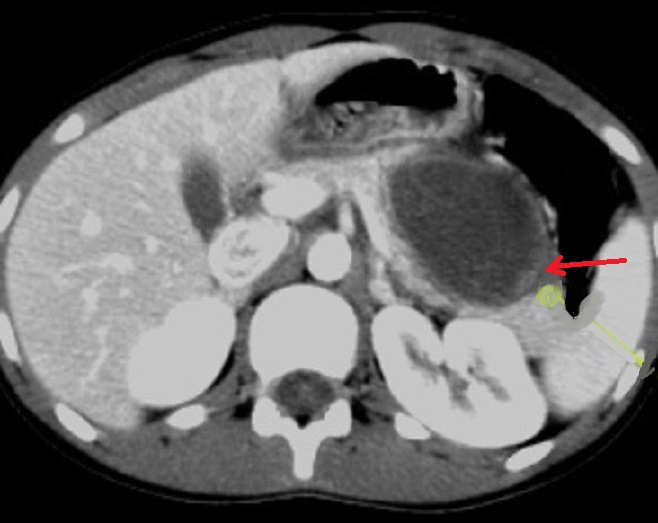

Image

radiologique TDM d'une lymphome pancreatique de la

tete du pancreas avec aspect lesionnel de forme

tumorale hypodense , homogene a mal limitee situe a

la tete du pancreas ( fleche rouge ) . Image TDM en

coupe axiale . |

|

Aspect lesionel TDM une masse a hypodense

, homogene mal limitee situe du corps pancreas(

fleche rouge . Rehaussement legere du tumeur apres

injection de contrast intraveineuse . Image

radiologique TDM plus contrast intraveineuse , coupe

axiale . |